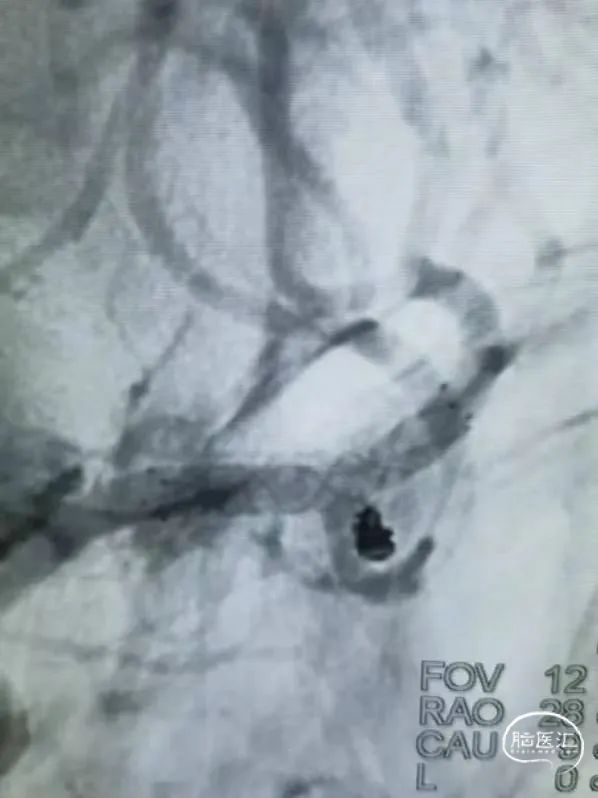

栓塞过程

3D圈成篮后,依次填入两枚Jasper®SS弹簧圈。

术后即刻影像

该病例为左侧大脑前动脉A3段动脉瘤破裂伴蛛网膜下腔出血,出血量相对少,无大面积血肿存在,该瘤体位于血管分叉部,瘤体不规则。在栓塞过程中,Jasper®SS系列弹簧圈的柔软性、顺应性表现良好,未见明显踢管现象,电解脱快速顺利,保证了手术的成功率,不仅提高了手术医师的自信心,更为患者的治疗带来了新福音。